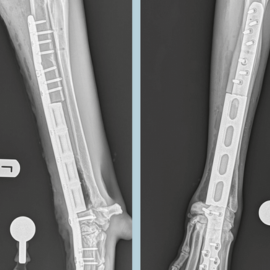

Resolución de fractura antigua de fémur mediante un nuevo sistema de clavo bloqueado.